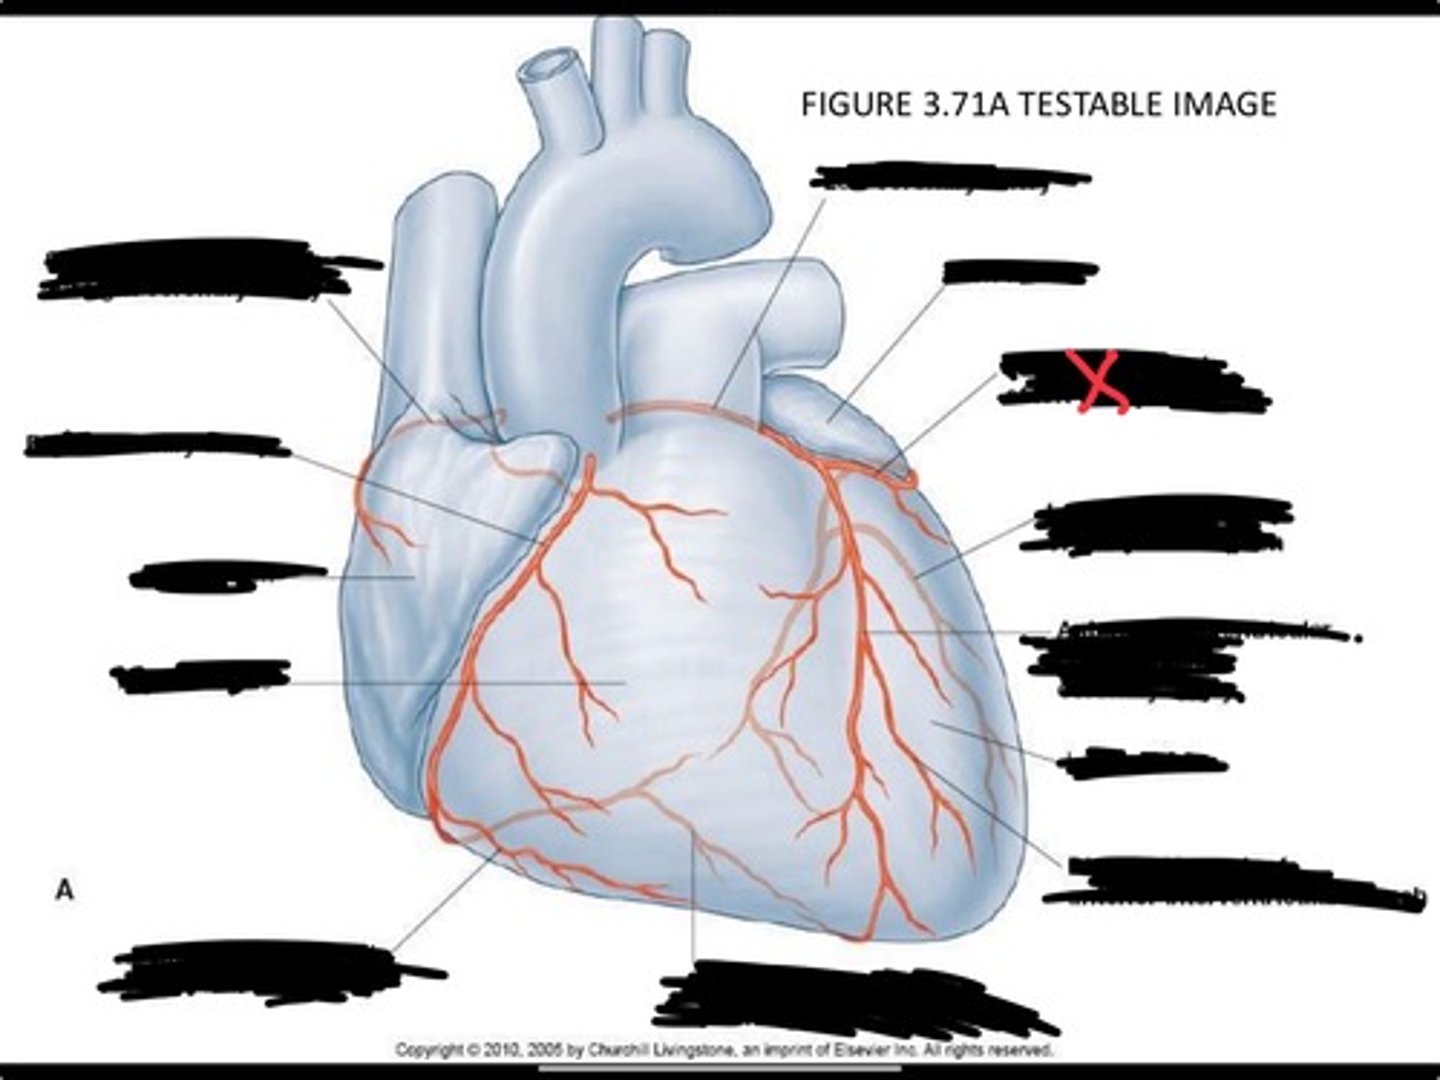

Posterior interventricular branch of right coronary artery

Right arginal branch of coronary artery

Right ventricle

Right atrium

Right coronary artery

Sinu-atrial nodal branch of right coronary artery

Left coronary artery

Left auricle

Circumflex branch of coronary artery